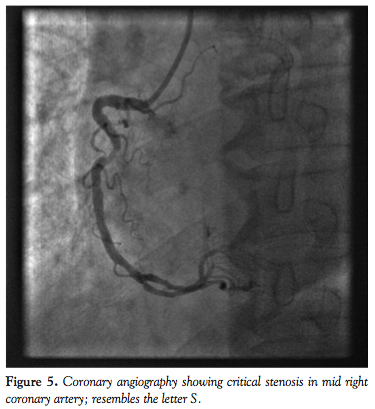

Based on the SYNTAX score criteria of severely tortuous lesions, 14 patients (40%) were found to have ≥1 bend of ≥90° on coronary angiography, with the remaining 21 patients (60%) having ≥3 bends of 45-90° proximal to the diseased segment. The majority of patients (80%) had multivessel disease on coronary angiography. The most common target vessel for PCI was left circumflex artery (LCX; 54.3%), followed by right coronary artery (RCA; 42.8%) and left anterior descending artery (LAD; 2.9%), with 37.1% of lesions located at the distal end of arteries. Moderate to heavy calcification was observed in 6 tortuous coronary vessels (17.1%). Transradial PCI was performed in 29 patients (83%) with a 6 Fr system the most commonly used (94.3%). Resolute Integrity drug-eluting stents (DESs) were implanted in 17 patients (49%). Mean stent diameter was 3.04 ± 0.51 mm and mean stent length was 20.5 + 6.6 mm. Glycoprotein IIb/IIIa inhibitors were used in 23 patients (65.7%).

Acute procedural success was achieved in 33 patients (94%) using conventional PCI techniques. Predilatation was performed in 31 patients (89%) and buddy wires were used in 12 patients (34.3%). For the 2 cases (6%) in which stent delivery failed, Heartrail catheters (the so-called “five-in-six” system; Terumo) were used as a bail-out to facilitate stent delivery. For the first Heartrail patient, the lesion was located in the distal RCA and the major impediment to stent delivery (besides the underlying tortuosity) was the presence of 3 long overlapping stents that were previously implanted in the proximal to mid RCA. The second Heartrail patient had lesions in the mid and distal RCA, but the stent passage was largely impeded by extreme tortuosity in the proximal RCA, which had moderate calcification.

For the overall study group, there were no peri- or postprocedural MACEs. Mean fluoroscopic time was 25.3 ± 17.2 minutes and mean contrast volume was 203.1 ± 80.1 mL. Figures 1 through 8 illustrate our experiences with Integrity coronary stents in some of the “classical” tortuous coronary vessels.

One striking feature we observed about the Integrity coronary stent was that it conformed very well to the vessel wall (Figures 1-8). This is important, since it means the stent has sufficient radial strength to resist the elastic recoil of the media and can mold its shape along the contour of a curved segment with minimal vessel straightening and provide a large desired lumen. When the DES is implanted, excellent apposition of the struts on the vessel wall will ensure uniform delivery of the cytostatic drug to prevent neointimal hyperplasia. An in vitro conformability test15 has shown the Integrity DES to have better strut apposition and lower vessel wall stress when compared to other market-leading DESs. This has